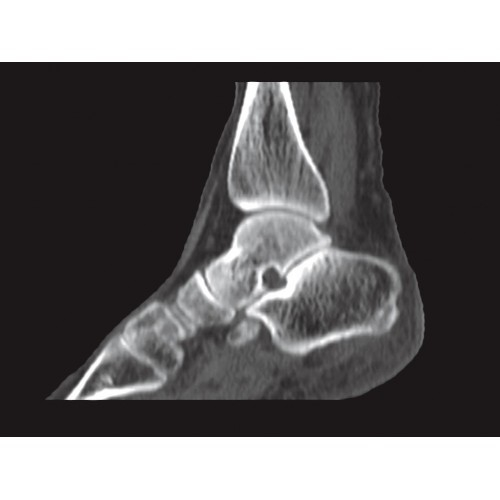

Обеспечивает высокую точность при кардиологических исследованиях, визуализации костных структур и суставов. Подходит для динамического наблюдения в ходе лечения.